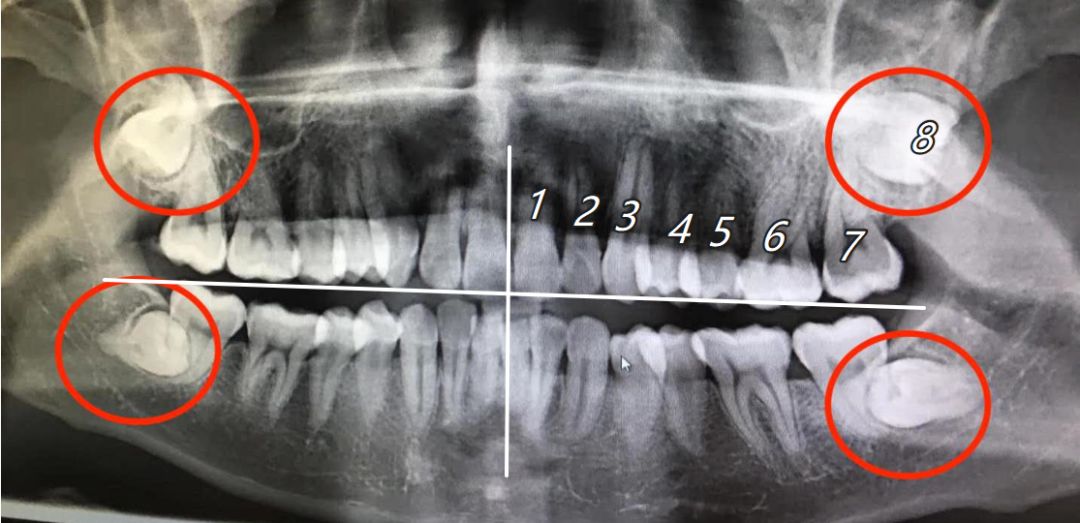

智齿又称“智慧齿”,现代人类的牙齿通常是28颗,上下左右各7颗,长出的第八颗牙齿通常称之为“智齿”。

红圈内为智齿